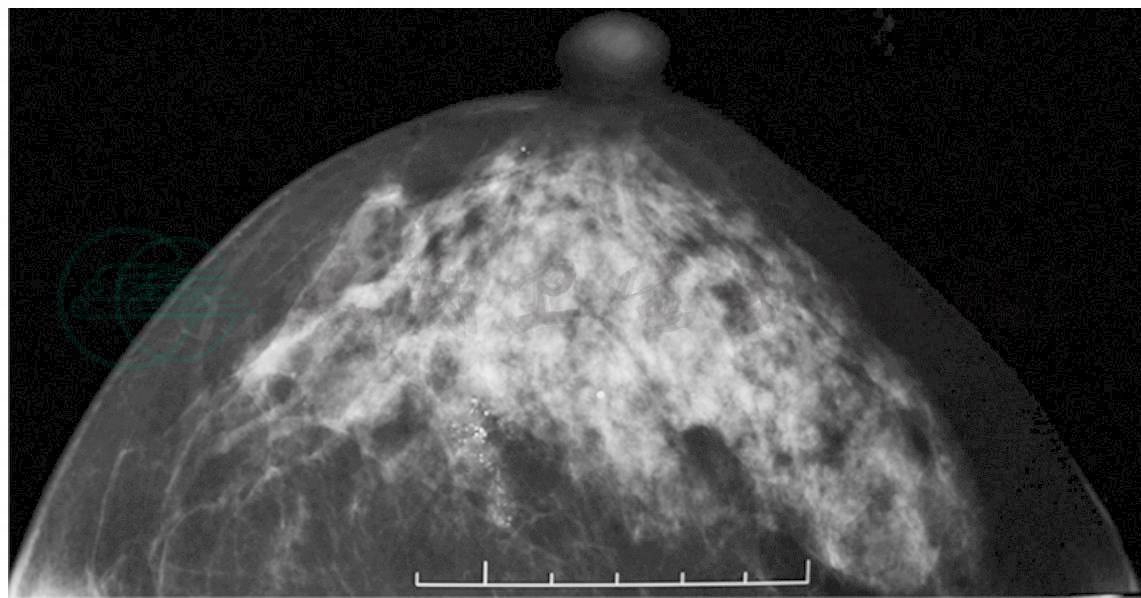

心、肺、腹(-),双乳对称,双乳头无内陷,双乳未触及明确肿物,双腋下与双锁骨上未触及肿大淋巴结。乳腺X线摄影(图1):右乳内下象限成簇微小钙化灶,BI-RADS 4类(可疑恶性),左乳两个钙化点,BI-RADS 2类(良性)。双乳超声与MRI均未发现占位性病灶。入院诊断为双乳钙化灶,右乳癌。入院后术前检查无手术禁忌证,于局麻下行“右乳钙化灶定位切除术”,术中冰冻病理证实为乳腺癌后,全麻下行“右乳癌改良根治术。”具体过程如下:

A. 右乳X线斜位显示下象限钙化灶

B. 右乳X线轴位显示外象限钙化灶

图1